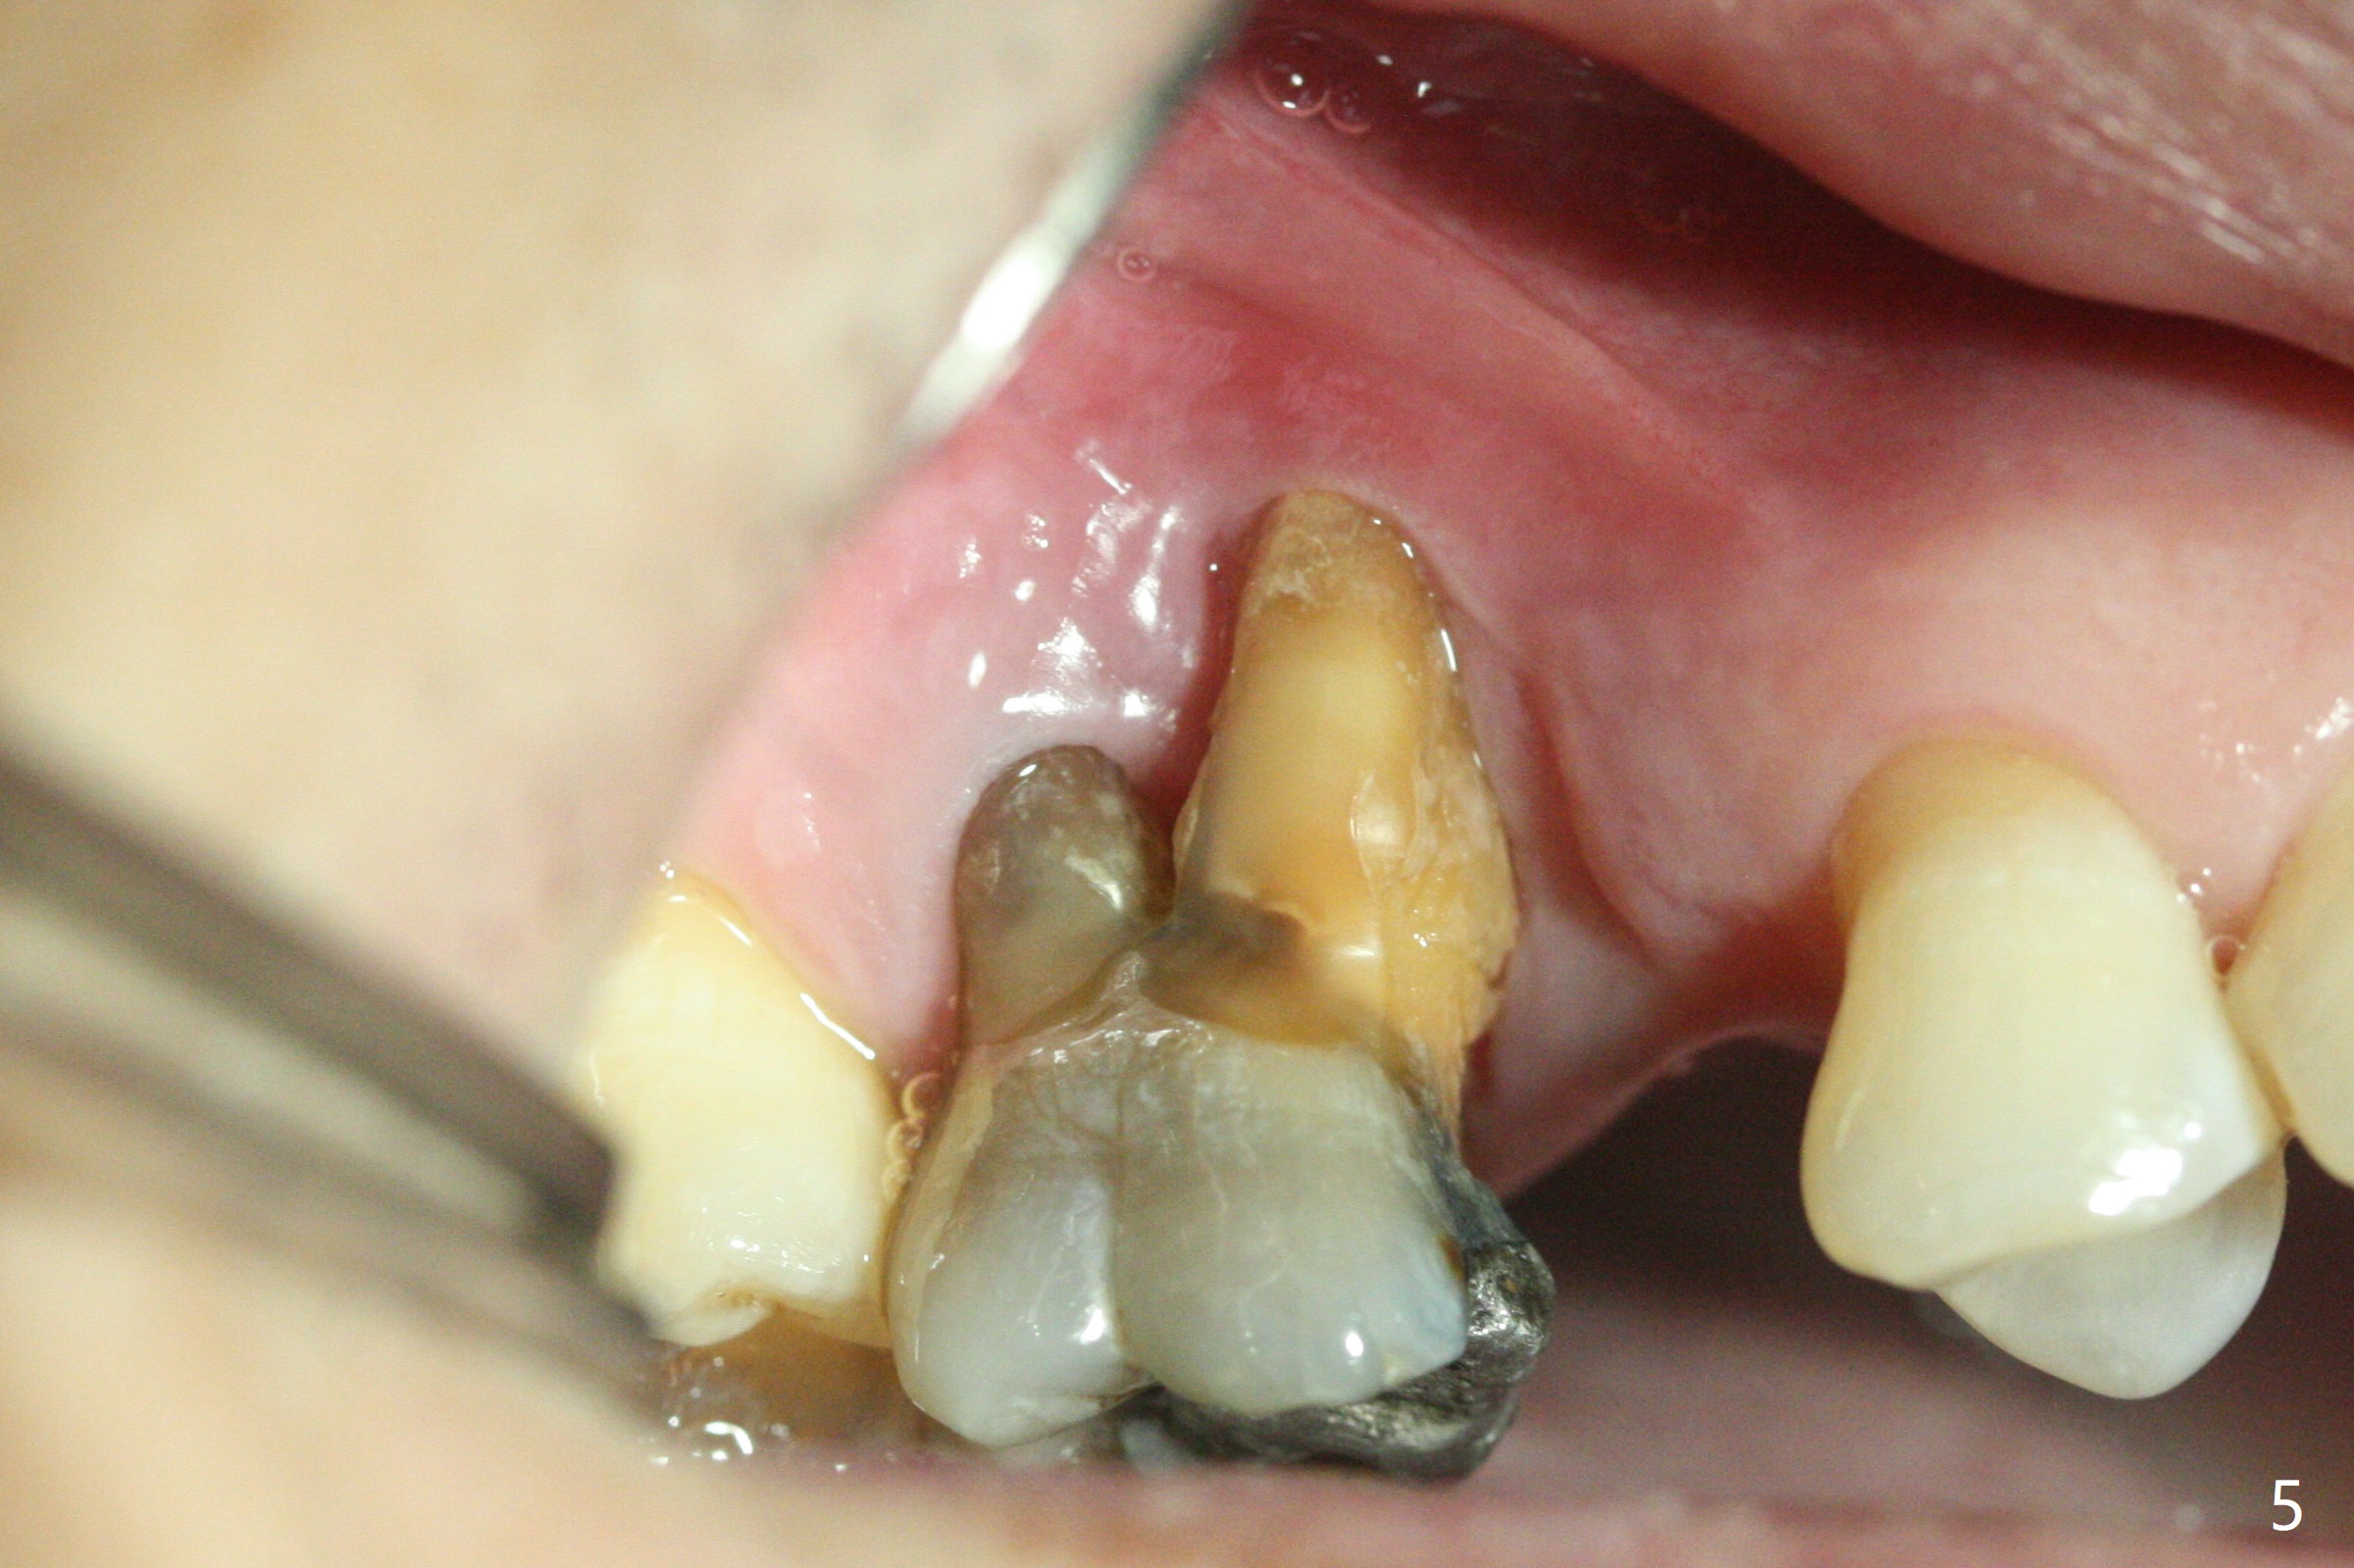

A 49-year-old man (patient of ours for 7 years) has severe bone loss and buccal recession at #3 with missing tooth at #4 (Fig.1,2,5). Short implants will be placed as palatal as possible (Fig.3,4 green) with buccal bone graft (red circles). PRF will be prepared for membranes and sticky bone.